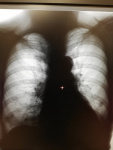

Проф флг что скажете?

Ваши мнения? Год назад не было такого

Больше похоже на фиброз. Иногда так выглядят рефлекторные субсегментарные ателектазы при катастрофах в брюшной плости.

Очень желательны боковые проекции.

Справа уплотненная малая междолевая. Слева, с учетом поломанных ребер( заднх отрезков 8-9ребер) тоже м.б. уплотнение по ходу главной междолевой, так и фиброателектаз.

Вот и мне кажется, что междолевая. Ателектаз в меньшей степени. Фиброз сомнительно, что за  но "с 0" и сразу вот так.